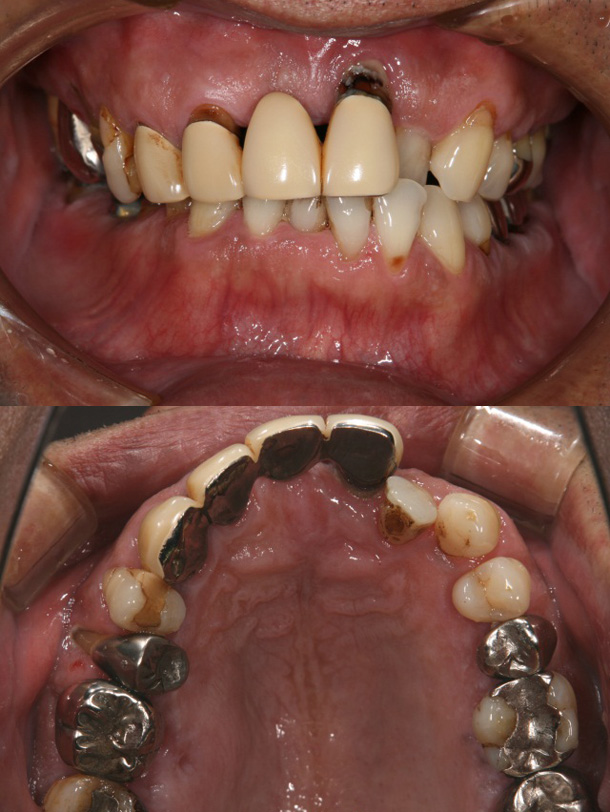

症例6:叢生による矯正治療後、上顎前歯・臼歯部をオールセラミッククラウンにて審美修復した症例

主訴:右下の冠がはずれた、前歯で咬めない

年齢:43歳

診断:上顎前歯酸蝕症による舌側エナメル質欠損、上下顎叢生、臼歯部反対咬合

装置:上下顎ブラケット装置

治療期間:2年1ヶ月(矯正治療)(来院回数24回)

抜歯:右下顎大臼歯の2本(むし歯によ)保存不可のため→インプラント治療を実施)

費用:750,000円+税

矯正前

矯正後

オールセラミックSET後